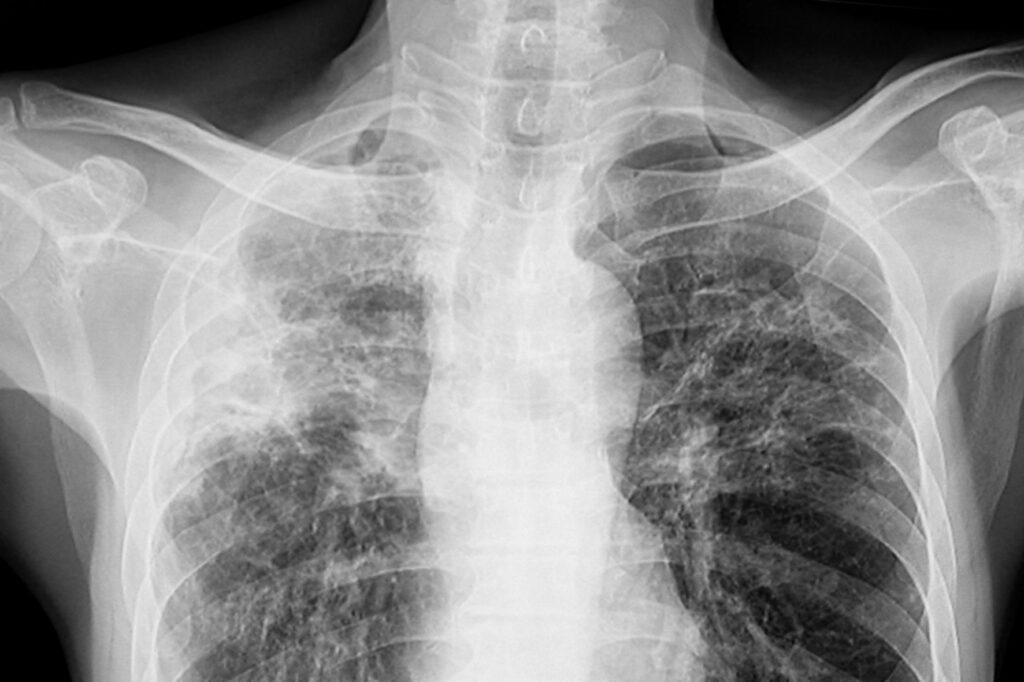

- RTG klatki piersiowej: Jest to podstawowe badanie obrazowe stosowane w diagnostyce gruźlicy. Na zdjęciach rentgenowskich można zaobserwować charakterystyczne zmiany w płucach, takie jak zmiany guzowate, zacienienia, czy przewlekłe zmiany zapalne.

Rozpoznanie gruźlicy na wczesnym etapie jest kluczowe dla skutecznego leczenia i kontroli choroby. Osoby, u których podejrzewa się gruźlicę ze względu na objawy lub czynniki ryzyka, powinny poddać się odpowiednim badaniom, takim jak badanie plwociny pod kątem obecności bakterii gruźlicy, badanie krwi, RTG klatki piersiowej, a także testy skórne czy testy interferonowe. Badania dodatkowe, takie jak tomografia komputerowa czy bronchoskopia, mogą być również wykonywane w celu potwierdzenia rozpoznania. Wczesne wykrycie gruźlicy umożliwia szybsze rozpoczęcie leczenia, co prowadzi do lepszych wyników terapeutycznych.